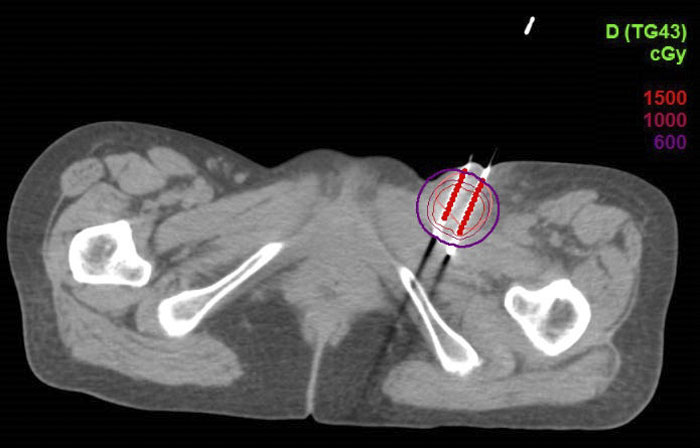

CT引导下的左侧腹股沟淋巴结组织间插植剂量图

CT引导下组织间插植近距离放疗是依据肿瘤形态及范围,制定插植针的排列及置入方向,将中空的金属针在CT引导下直接插入肿瘤组织内,再进行CT扫描,在治疗计划系统中勾画靶区,由物理师进行靶区剂量优化及危及器官限量。计划完成后,通过传输管将插植针与放射源相连接;通过计算机控制,将放射源输入插植针进行放射治疗,待结束后,放射源回收到贮源器内,保证患者体内无放射源残留。组织间插植使用铱192放射源,由于射线能量与距离成平方反比,可在肿瘤靶区内形成高剂量,而周围正常组织剂量极低,从而实现最大限度的肿瘤杀伤,且非常安全。